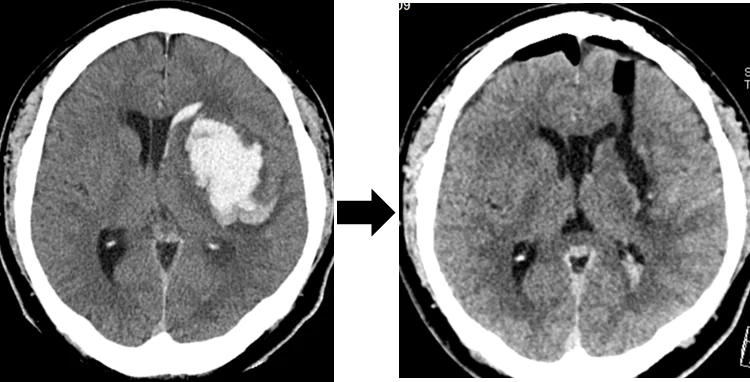

水頭症ではシャント留置が不要な第3脳室底開窓術を行っています。また、脳内出血や脳腫瘍においても従来の開頭手術ではなく、穿頭/小開頭で内視鏡下の腫瘍摘出や血腫除去術を積極的に取り組んでいます。

内視鏡による脳内血腫の除去 (左: 手術前 右: 手術後)